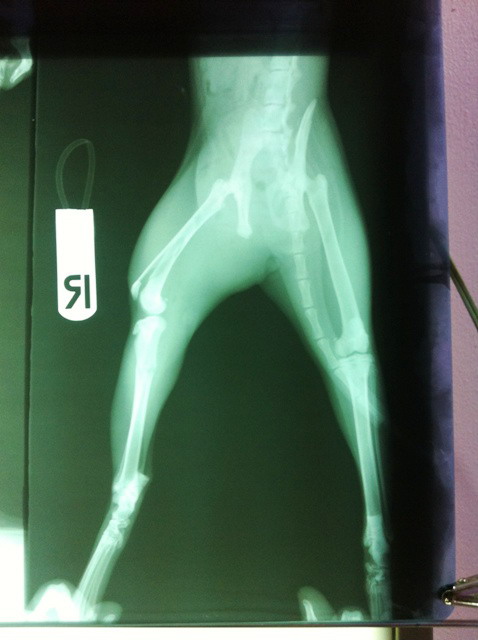

แฟนผม เข้าไปเคลียร์งาน ประมาณ 1 ชม. ก็พาเจ้าดำตัวน้อย ขึ้นแท๊กซี่ ไป รพ. สัตว์ลาดกระบัง คุณหมอเลยจัดการตรวจสอบทั่วไป ผลร่างกายแข็งแรง แต่ทว่า เมื่อจับเจ้าดำน้อย X-Ray ปรากฏว่า " เจ้าดำน้อย ขาหัก ตั้งแต่สะโพก ลงไป 3 ท่อนครับ

"

คุณหมอบอกว่าน่าจะโดนตีมา มากกว่าโดนรถชน หรือกระโดดลงมาจากที่สูง ถ้าเป็นอย่างที่หมอว่า คนทำคงจะใจร้ายน่าดู

ก็เลยทำการรักษาด้วยการเข้าเฝือก และ คุณหมอให้ยาแก้ปวดมากิน พร้อมทั้งยาแคลเซียม และให้กักบริเวณ ไว้ก่อน พร้อมทั้งนัดมาเช็คเฝือก และ นัดมา X-Ray ในอาทิตย์นี้